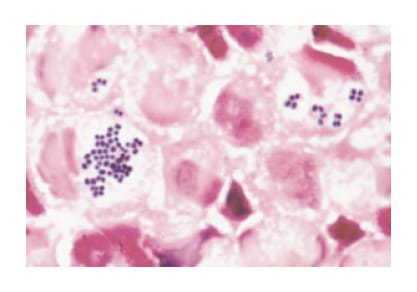

Once a specimen has been collected, 3 days are required to determine the causative pathogenic microorganism and its susceptibility (Table 2). Empiric therapy is initiated against the suspected pathogenic microorganism. Gram staining, which takes about 15 minutes, is performed to further narrow down the causative microorganism. Figure 3 shows phagocytized gram-positive cocci that have been Gram-stained. Since the bacteria look like grapes, indicating that they are staphylococci. Knowing it is a staphylococcal bacterium, even though the species has not been identified and drug susceptibility data are pending, cefazolin or vancomycin can be recommended.

Fig. 3 Detection of gram-positive cocci with Gram staining

Source: Nagata K., Gram Staining Informs Infection

Diagnosis. p. 15, 2006 [in Japanese].